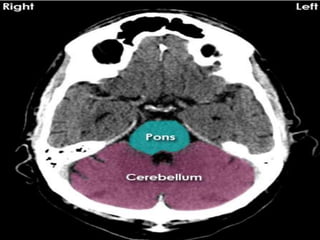

• Brainstem.

Pontine bleed